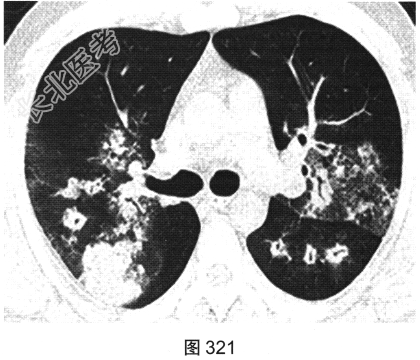

- [材料题] 患者男性,30岁,发作性咳喘3年,吸入冷空气后鼻塞、流黄白色脓涕,外院予环丙沙星治疗后症状缓解,其后鼻塞,夜间睡眠中喘憋反复发作;咯血、发热1周,以傍晚和夜间为著,体温最高为38.5℃,伴畏寒及周身疼痛,痰中带血,为鲜红色,伴胸痛、咳嗽,喘憋明显。胸部CT检查如图319~图324所示。

- 多项选择题1.在提供的CT平扫图像上,可观察到下列哪些影像学征象( )

A、晕征

B、双肺结节影

C、小叶间隔增厚

D、反晕征

E、小叶中心结节

F、双肺磨玻璃影、斑片实变影

G、支气管壁增厚、管腔扩张、支气管充气征

- 多项选择题2.该患者病变的主要分布特点为( )

A、肺中央分布为主

B、肺外周分布为主

C、支气管血管束周围分布为主

D、上肺分布为主

E、随机分布

F、下肺分布为主